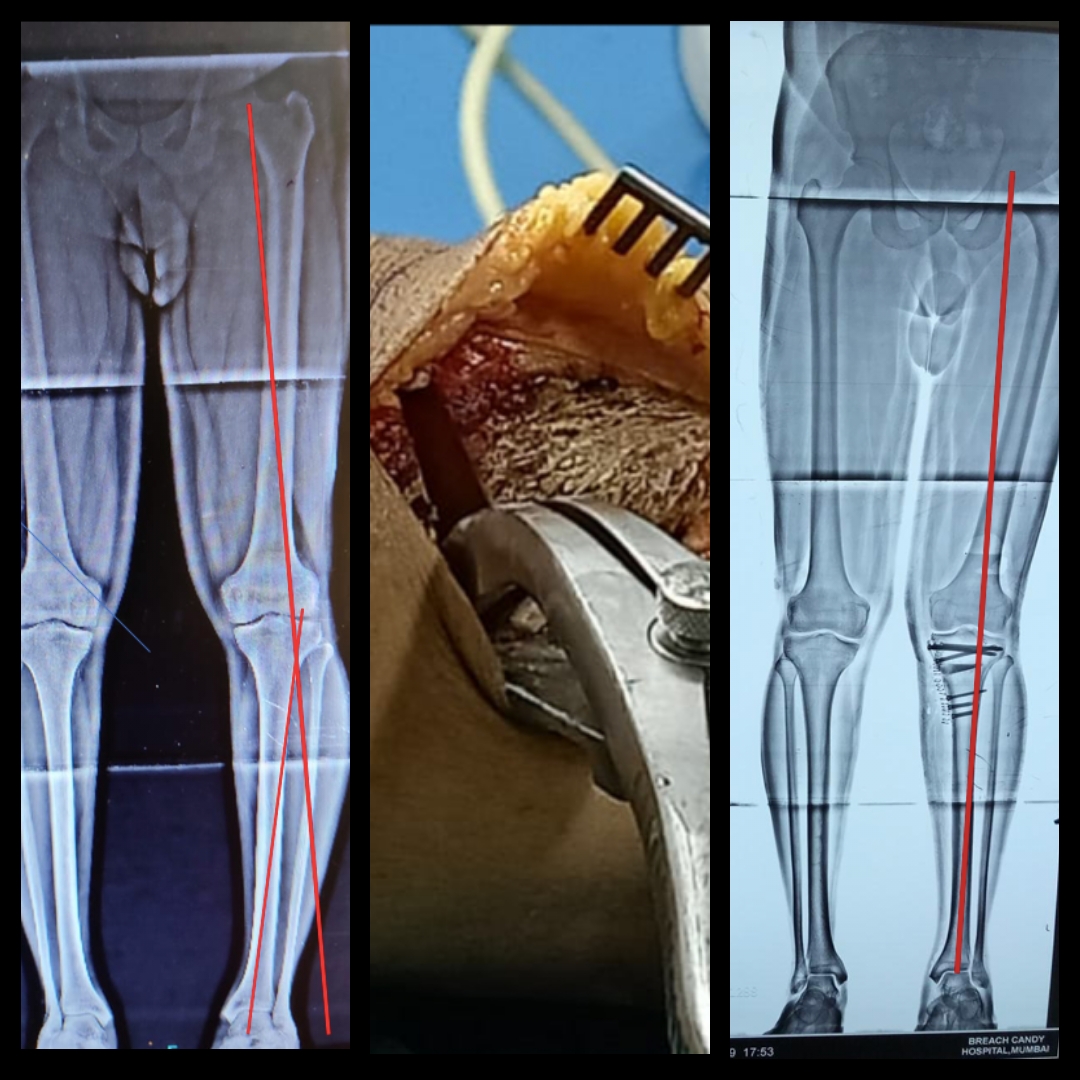

History: 41-yr-old man was suffering from immense pain in his left knee and standing scanogram showed a varus malalignment whereas MRI showed a medial meniscus tear. Case: A plain arthroscopic meniscectomy would not have relieved his symptoms. Normal mechanical axis…